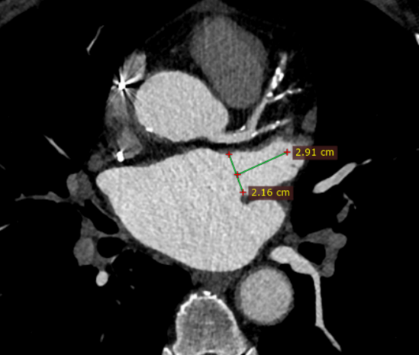

术前ct评估:心耳内确认无血栓,测量心耳开口21.6mm,深度29mm

术前cta:左心耳开口切面利用ct数据三维重建获悉,左心耳开口长轴26.